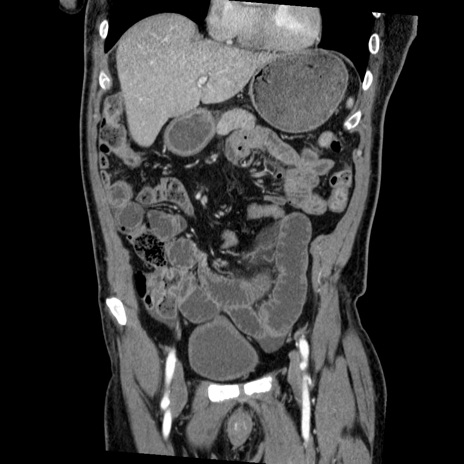

横断像

【症例】50歳代男性

【主訴】腹痛

【現病歴】AVMからの被殻出血のため回復期リハ病棟入院中。 本日午後3時頃急に下腹部痛が出現した。

【既往歴】AVM、被殻出血、虫垂炎、高血圧

【身体所見】意識晴明、左半身不全麻痺、会話の理解は良好、36.5°C、腹部:膨隆、全体に板状硬、下腹部正中に圧痛点あり、反跳痛-、筋性防御不明、右下腹部にope scar

【データ】WBC 9400、CRP 0.06